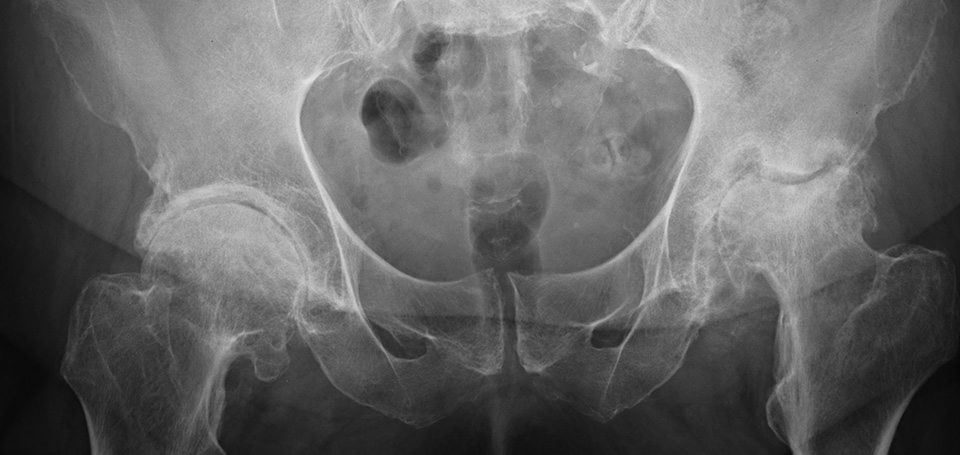

После установки искусственного тазобедренного сустава в течение 3 недель пациент находится в хирургическом стационаре. Затем реабилитация может проходить в течение месяца в специализированных центрах или в домашних условиях. Для полного восстановления ТБС требуется от 3 до 4 месяцев. На продолжительность реабилитации влияет возраст, вес пациента, тяжесть течения патологии, физическая подготовка. Немаловажен и метод хирургического вмешательства. Период восстановления несколько короче при однополюсном протезировании — замене только головки бедренной кости. Если устанавливается и искусственная вертлужная впадина, то для разработки сустава потребуется больше времени.